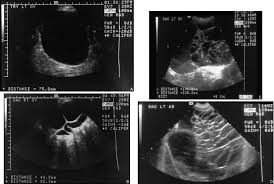

Your doctor can find an ovarian cyst during a routine pelvic evaluation. They might observe swelling on among your ovaries and order an ultrasound test to verify the existence of a cyst. Surgery for a worsening medical condition or to check for cancer. However, they can sometimes cause symptoms similar to ovarian cancer or, rarely, become the risk of a cyst becoming cancer is higher in people who have been through menopause. Ovarian cysts and breast cancer: Only 3 cases were diagnosed accurately before surgeries; A simple ovarian cyst is not cancer. Ovarian cysts are either benign or malignant. Current research suggests this cancer begins in the fallopian tubes and moves to the ovaries, the twin organs that produce a woman's eggs and the main source of the female hormones estrogen and progesterone. Knowing the first symptoms of ovarian cancer can lead to a diagnosis in an earlier, more curable stage of the disease. There are more actual cases of olive leaf. A cyst on your ovary can be found during a pelvic exam. Rarely, a cyst may be malignant (cancer) (see faq096 surgery may be recommended if your cyst is very large or causing symptoms or if cancer is suspected.

What Does Ovarian Cancer Look Like / What are the Signs & Symptoms? - National Ovarian Cancer ... - Wednesday 25 february is ovarian cancer awareness day. . Most ovarian cysts go away with time. This type of cancer can occur in women who still have their ovaries, but it is of more concern for women who have had their ovaries removed to. What does ovarian cancer look like on an ultrasound? Like ovarian cancer, ppc tends to spread along the surfaces of the pelvis and abdomen, so it is often difficult to tell exactly where the cancer first started. I'm sharing my story in the hope of raising awareness about this devastating disease, and to help raise funds for important australian medical research currently being. Department of health and human services national institutes of it is the most common type of ovarian cancer. What does ovarian cancer look like on an ultrasound? Ovarian cancer is highly curable if it's diagnosed and treated early, but the symptom...